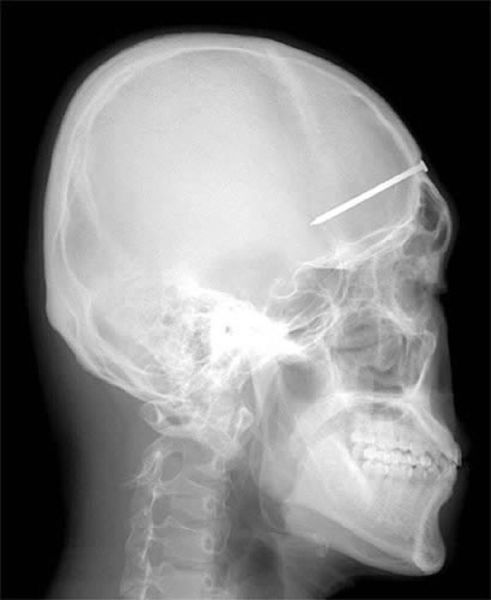

A dentist found the source of the toothache Patrick Lawler was complaining about on the roof of his mouth: a four-inch (10-centimeter) nail the construction worker had unknowingly embedded in his skull six days earlier.

A 16-year-old cheated death when a 5-inch knife was plunged into his head. The teenager was rushed to hospital with the kitchen knife still stuck in his forehead.

The 5-centimeter nail shown in this X-ray was found after a man came to a Seoul, South Korea, hospital complaining of a severe headache. After examining and interviewing the man, doctors speculated that the nail had been the result of an accident four years before his visit, but that the man did not know the nail was lodged in his head.